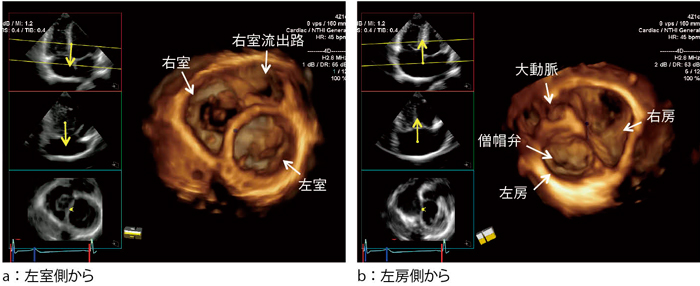

実践3D心エコー図法